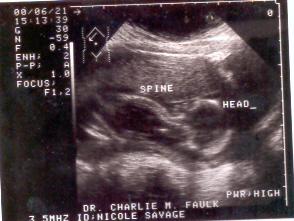

This is the first ultrasound picture I got when I

was in the hospital. I was 8 weeks pregnant when

this was taken.

This was my second ultrasound picture. I went to

office for this one. I was about 4 months pregnant,

I think 14 weeks.

This was my second ultrasound picture also. He gave

me two that day. This was the last time I ever saw

my baby on screen.